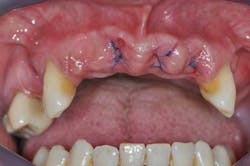

Figs. 3a, b, and c: Extraction of the upper incisors and maxillary removable acrylic placement